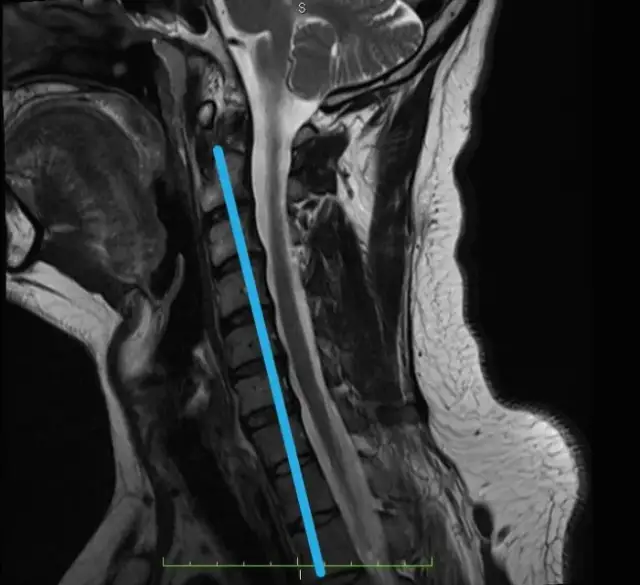

Ile trwa leczenie skręcenia kręgosłupa szyjnego? Poznaj konkretne ramy czasowe, etapy rekonwalescencji i czynniki wpływające na powrót do zdrowia.